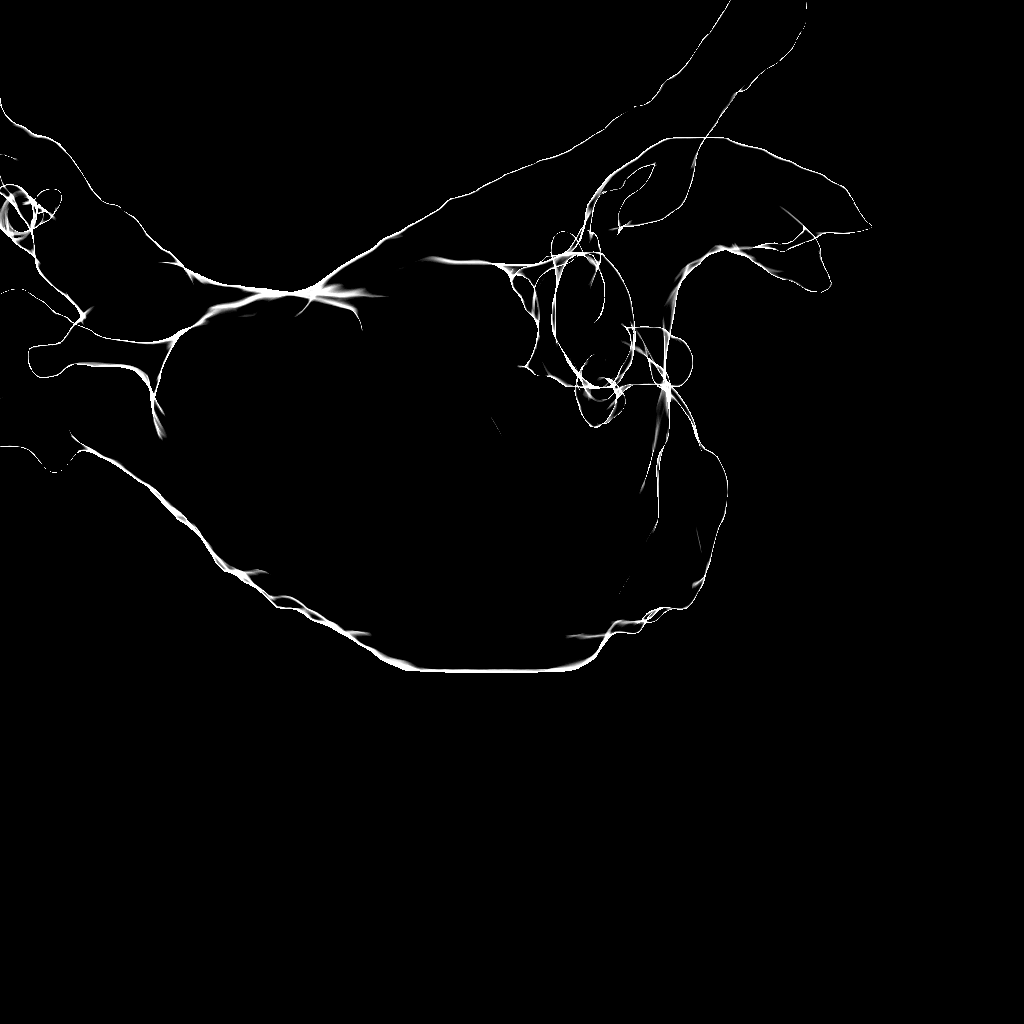

II-B Edge Feature

Unfortunately, a registration approach only based on contrasted area has multiple solutions if the amount of CA is so little that it can be located at different positions inside the LA, see Figure 1. Often, CA is injected against the roof or into the pulmonary veins. This results in perceivable edges of the contrasted area which can be used as registration features as well. Edge-based registration can be done using only the silhouette boundary of the projected object [7], see Figure 1 or all apparent edges [3, 4], see Figure 2.

We decided to go for the second approach, as the silhouette corresponds to the edges in the image only if the complete atrium is filled with contrast. For a partially contrasted left atrium, internal contours may, however, also appear in the fluoroscopic images. This was already found to be beneficial for manual LA registration [5]. Instead of considering edges implicitly by comparing the DSA image to a DRR using gradient correlation [10], we computed them explicitly. To extract edges in the fluoroscopic images, we used the previously computed filtered image . After applying a median filter, edge-like variations inside the contrasted areas may remain. They would trigger a response, if an edge filter was applied. To obtain an edge response only at the boundaries of the contrasted area, the image needs to be homogenized before applying an edge filter. Using a simple threshold method would result in a loss of the intensity drop-off at the boundary which provides important information about the edge intensity. Therefore, we weigh all image pixels by a sigmoid function